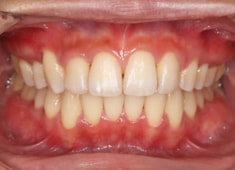

治療後(2年後)